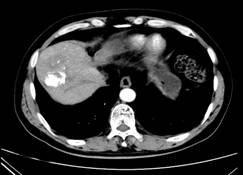

张××,男,56岁,外院CT增强示肝右叶“巨块型肝癌”,首次介入治疗后复查CT(2012年4月25日)所见瘤体大部栓塞,周围组织损伤小(图1a~b)。3年9个月后复查(2016年1月21日)见原瘤体明显缩小,上方肝实质复发病灶(图2a~b)。

图1a 图1b

图2a 图2b